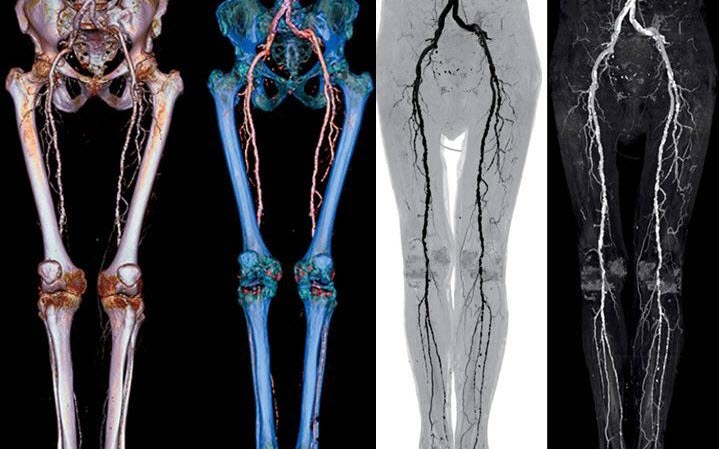

- Ультразвуковая диагностика (дуплексное сканирование: стандартная методика в сочетании с допплеровским исследованием). В ходе процедуры измеряется кровоток в изменённых сосудах, который при наличии заболевания значительно снижен.

- Компьютерная томография с контрастированием – помогает определить процент окклюзии по сравнению со здоровой частью артерии и длину поражённого участка. Этот метод используется не только для диагностики, но и для подготовки к хирургическому вмешательству.

- Контрастная ангиография. Применяется, если планируется инструментальная терапия с хирургическим вмешательством.

- Магнитно-резонансная ангиография – менее предпочтительная альтернатива вышеуказанным методам.